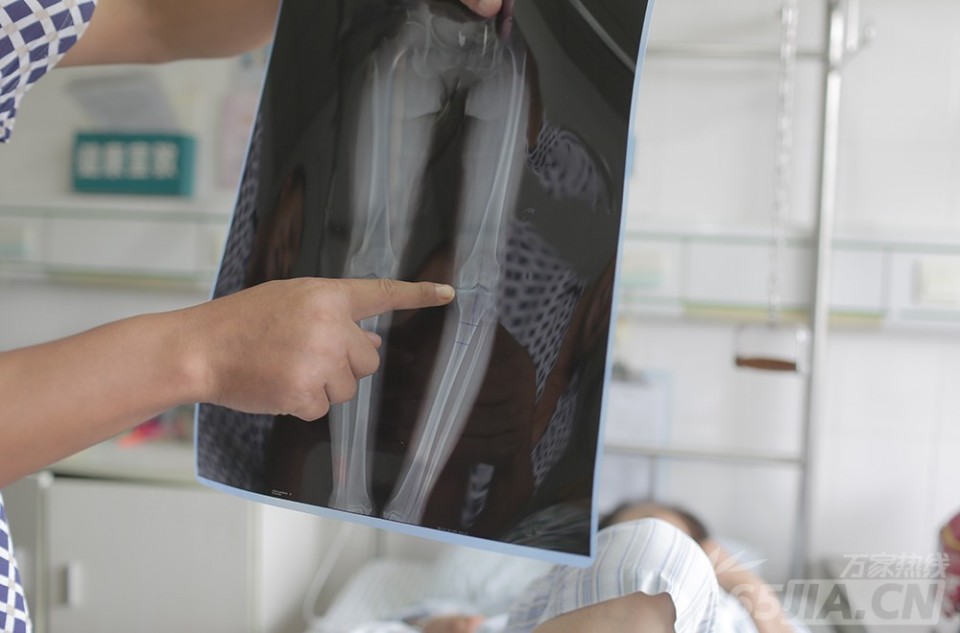

从8月3日住院以来,唐大妈儿子一直在医院陪护,拿起膝盖X光片,介绍其母亲的病情,“我们农村医疗条件有限,给小诊所耽误了,你看膝盖这边都有点变形,到大医院我们才知道我妈这是膝盖出问题。她现在已经疼到不能走路,出门只能骑电动三轮车。”